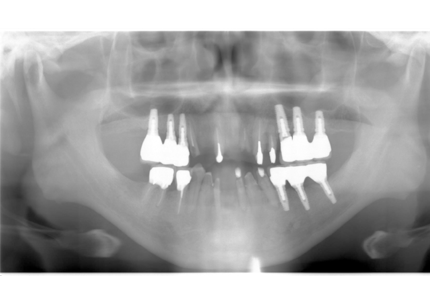

18.インプラント埋入後 パノラマレントゲン

【受傷時 2018年5月17日】

【受傷時 パノラマレントゲン】

【最終補綴物装着 パノラマレントゲン】